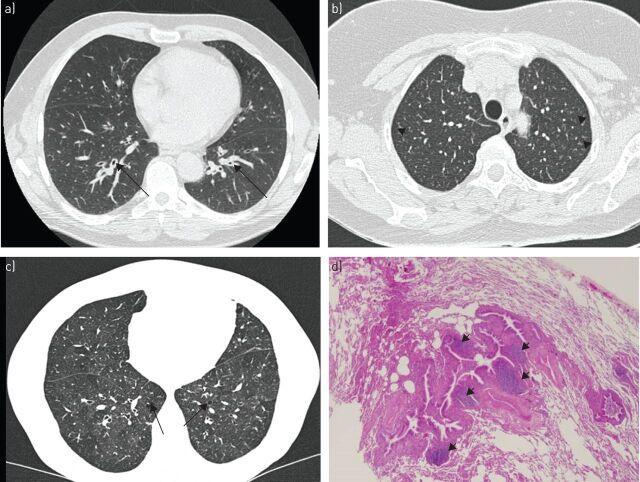

In 9-20% of cases, Sjögren's syndrome is associated with various respiratory symptoms. The most typical manifestations are chronic interstitial lung disease (ILD) and tracheobronchial disease. The most common manifestation of ILD is nonspecific interstitial pneumonia in its fibrosing variant. Other types of ILD, such as organising pneumonia, usual interstitial pneumonia and lymphocytic interstitial pneumonitis, are rare. Their radiological presentation is less distinctive, and definitive diagnosis may require the use of transbronchial or surgical lung biopsy. Corticosteroid therapy is the mainstay of ILD treatment in Sjögren's syndrome, but the use of other immunosuppressive drugs needs to be determined. ILD is a significant cause of death in Sjögren's syndrome. Tracheobronchial disease is common in Sjögren's syndrome, characterised by diffuse lymphocytic infiltration of the airway. It is sometimes responsible for a crippling chronic cough. It can also present in the form of bronchial hyperresponsiveness, bronchiectasis, bronchiolitis or recurrent respiratory infections. The management of these manifestations may require treatment for dryness and/or inflammation of the airways. Airway disease has little effect on respiratory function and is rarely the cause of death in Sjögren's syndrome patients. Rare respiratory complications such as amyloidosis, lymphoma or pulmonary hypertension should not be disregarded in Sjögren's syndrome patients.

在9%至20%的病例中,干燥综合征与多种呼吸道症状相关。最典型的表现是慢性间质性肺疾病(ILD)和气管支气管疾病。ILD最常见的表现是纤维化型非特异性间质性肺炎。其他类型的ILD,如机化性肺炎、寻常型间质性肺炎和淋巴细胞间质性肺炎则较为罕见。它们的影像学表现不太具有特征性,明确诊断可能需要进行经支气管或外科肺活检。糖皮质激素治疗是干燥综合征中ILD治疗的主要手段,但其他免疫抑制药物的使用需要确定。ILD是干燥综合征患者死亡的重要原因。气管支气管疾病在干燥综合征中很常见,其特征是气道弥漫性淋巴细胞浸润。它有时会导致严重的慢性咳嗽。它也可能表现为支气管高反应性、支气管扩张、细支气管炎或反复呼吸道感染。这些表现的管理可能需要对气道干燥和/或炎症进行治疗。气道疾病对呼吸功能影响较小,很少是干燥综合征患者死亡的原因。干燥综合征患者不应忽视罕见的呼吸道并发症,如淀粉样变性、淋巴瘤或肺动脉高压。